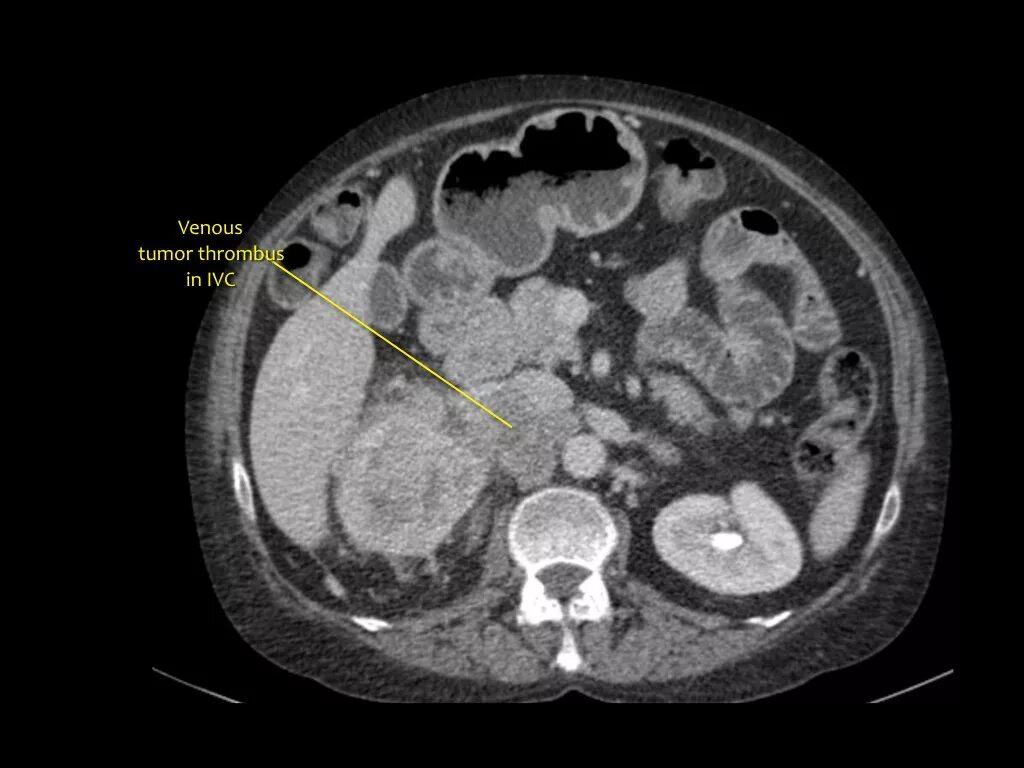

Солидное образование форум